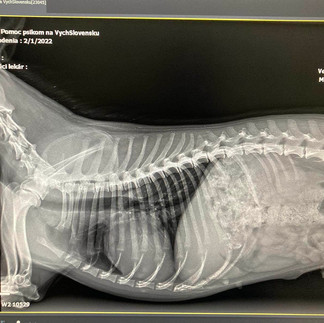

Lilli wurde von einem Passanten leblos auf der Straße liegend gefunden. Sie wurde von einem Auto angefahren und konnte die Straße nicht alleine verlassen, sie erlitt mehrere Brüche. In der Tierklinik wurde festgestellt, dass sie einen Oberschenkel-, Hüft- und Beckenbruch hatte. So einen schweren Fall hatten wir noch nie, erzählt Janka.

Die Operation: Lilli wurde operiert. Die Ärzte verbanden die gebrochenen Knochen auf beiden Seiten ihres Beckens und Oberschenkels mit Schrauben. Lilli bleibt einige Tage im Krankenhaus, bevor sie in Jankas Obhut gehen kann.